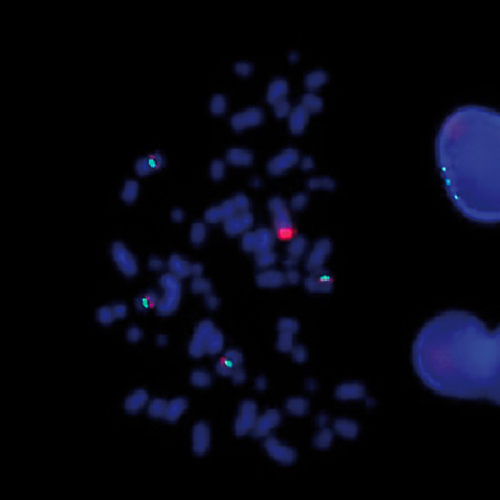

SS18 (18q11) Break probe hybridized to patient material showing translocation of the SYT (SS18) gene region at 18q11 (1RG1R1G).

The characteristic chromosomal abnormality in Synovial Sarcoma t(X;18)(p11.2;q11.2) is present in 90% of the patients. This translocation results in the fusion of the synovial sarcoma translocation, chromosome 18 (SS18) gene to either of two distinct genes, SSX1 or SSX2, located on the X chromosome. The SS18 (18q11) Break probe is optimized to detect translocations involving the SS18 gene region at 18q11 in a dual-color, split assay on paraffin embedded tissue sections.